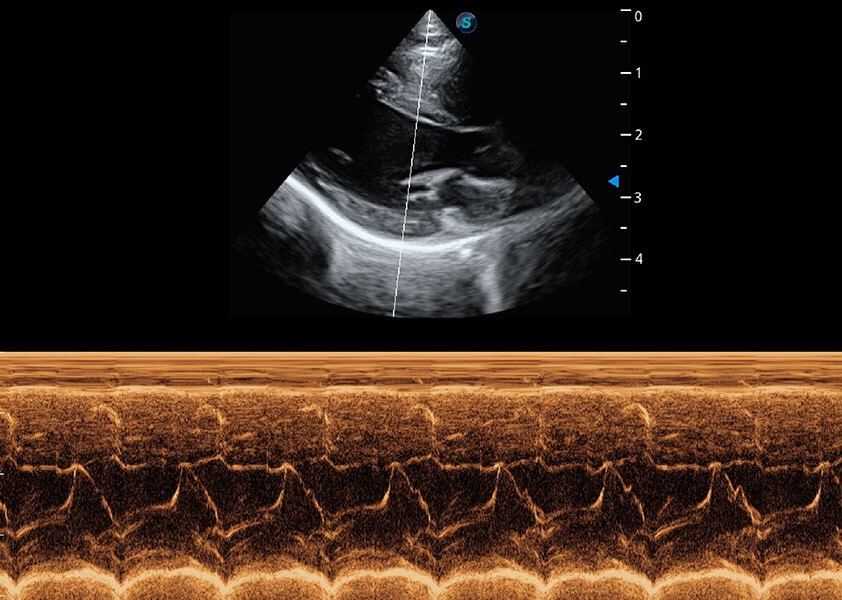

优异的基础图像

(猫)二尖瓣M型

• AMM 解剖M型

通过360度任意调节3条M型取样线,在同一心动周期上观察心脏不同位置的运动曲线,得到准确的心功能测量数据,有效评估心肌运动及左心室功能。